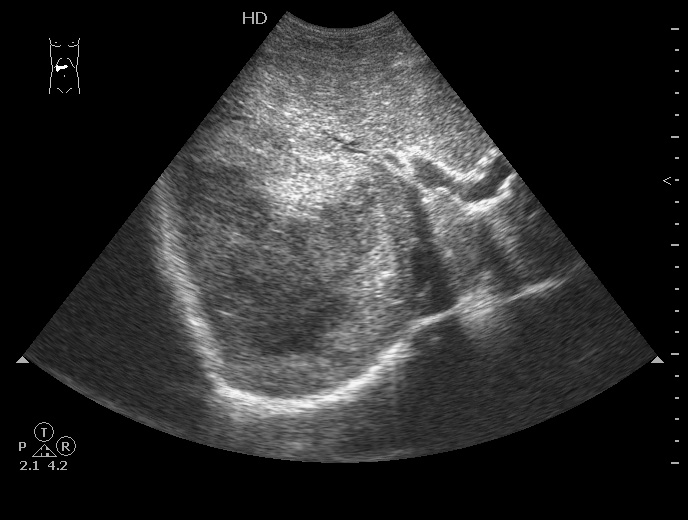

На следующий день сонографическая картина немного изменилась:

12-07-26-105134_6046_201207.jpg

Какие мысли?

на узи на абсцесс не похоже, образование солидное ----гепатома?

Гигантская капилярная гемангиома печени.

Ангиографию надо назначить или УЗИ с контрастированием.